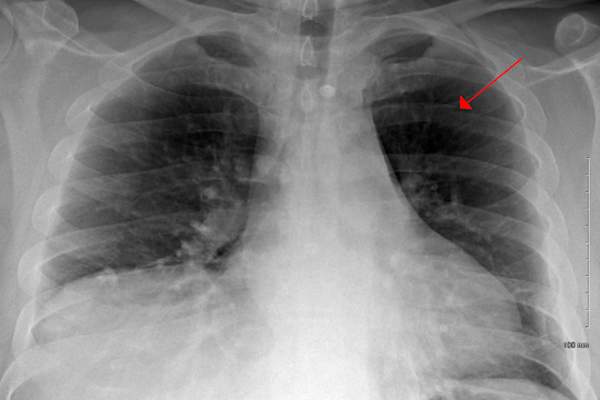

即使它的早期发现,一些肺癌患者都不是健康的还是强大到足以接受手术切除肿瘤。这是罗伯特Tumanic,一个69岁的财务顾问居住威斯康星州密尔沃基附近的情况。就在2015年被诊断出患有早期肺癌后(他有两个他的肺肿瘤),医生还发现他也有慢性阻塞性肺病(COPD),一种疾病,影响正常呼吸。

通常情况下,当癌症仅位于肺部,并没有扩散到淋巴结,和人是原本健康,医生建议通过手术切除肿瘤罗德尼韦格纳,医学博士,肿瘤学家阿勒格尼健康网门罗维尔,PA辐射说。

根据肿瘤的位置,大小和阶段,手术是所有的病人可能需要,虽然在很多情况下,医生也建议用化疗或免疫跟进,以确保所有的癌细胞消灭。